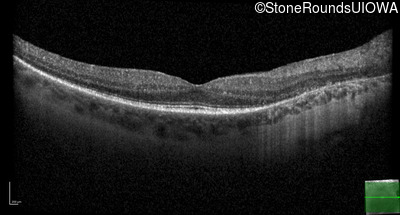

OCT Stack

20/32